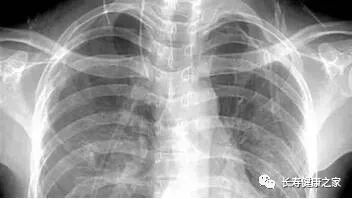

X光

像把面包压扁了看

X光会穿过人体,遇到被遮挡的部位,底片上不会曝光,洗片后这个部位就是白色的。

就像一片面包或一块棉花,看不到里面的纤维纹理,但用手压瘪了会清晰一些。X光最大缺点是受制于深浅组织的影像相互重叠和隐藏,有时需要多次多角度拍摄X光片。

胸  部

粗看X光片,细看CT

X光胸片可粗略检查心脏、主动脉、肺、胸膜、肋骨等,可以检查有无肺纹理增多、肺部钙化点、主动脉结钙化等。

胸部CT检查显示出的结构更清晰,对胸部病变检出敏感性和显示病变的准确性均优于常规X光胸片,特别是对于早期肺癌确诊有决定性意义。

但是CT检查的辐射剂量高于X光。核磁对于肺部疾病的诊断,应用非常有限。